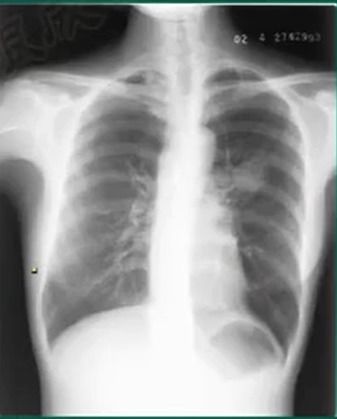

在疾病的早期筛查😁与诊断中,医学影像扮演着至关重要的角色,而胸片作为最常见的影像学检查手段之一,其图像质量的优劣直接关系到诊断的准确性。长期以来,胸片曝光的精准控制一直是影像科医生面临的一大挑战。曝光不足可能导致病灶模糊不清,容易漏诊;曝光过度则会使图像细节丢失,增加误诊的风险。

每一次的调整都可能是一场与“恰到好处”的博弈。随着科技的飞速发展,“100%胸片曝光软件”的出现,正以前所未有的力量,彻底改变着这一局面,将胸片影像的精准度推向了一个全新的高度。

这款软件的核心,在于其对曝光参数的极致追求与智能调控。它不仅仅是一个简单的图像处理工具,更是一个集成了先进物理模型和人工智能算法的精密系统。在传统胸片拍摄过程中,曝光参数的设定往往依赖于摄影师的经验和设备本身的自动曝光系统。这种方式存在着固有的局限性,难以适应各种体型、不同胸腔密度的患者,也无法完全捕捉到🌸最微小的病灶细节。

而“100%胸片曝光软件”则通过深度学习和大数据分析,建立了一个庞大的胸片曝光数据库。它能够根据患者的实际情况,如胸腔厚度、骨骼密度、呼吸配合程度等,进行多维度、高精度的分析,并智能推荐最优的曝光组合。这就像是为每一位患者量身定制了一份“曝光方案”,确保在保证足够信息量的将图像的噪声降到最低,细节展现到最清晰。